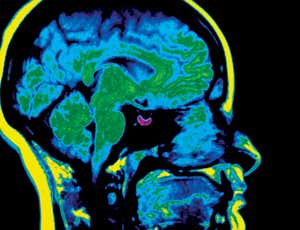

A fully-functioning pituitary gland has been grown out of embryonic stem cells and successfully transplanted into mice (Image: Scott Camazine/Science Photo Library)

The pituitary gland houses a factory of hormone-producing cells. Stress responses, energy use and growth are all regulated by signals that originate in this pea-sized section of brain, which sits near the base of the skull.